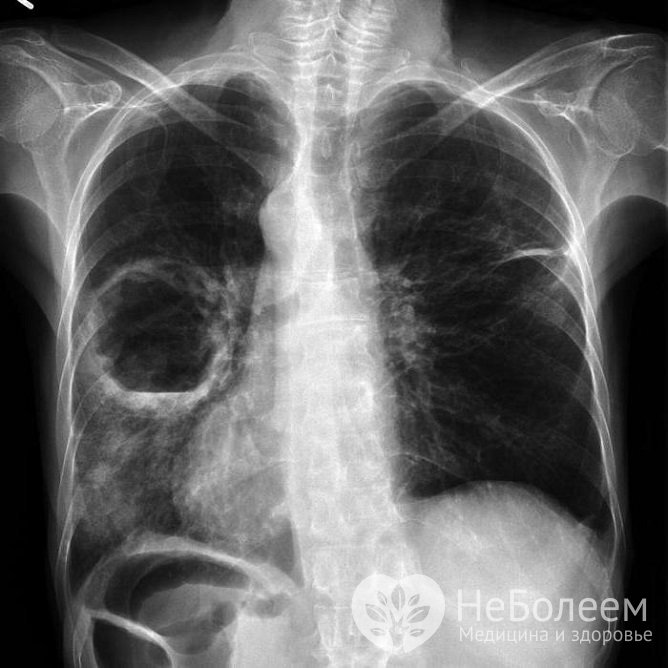

Клинический анализ крови имеет важное диагностическое значениеНа рентгенограмме грудной клетки определяется диффузное двустороннее затемнение легочных полей или прогрессирующие диффузные изменения по типу матового стекла и консолидация. На снимках видно диффузное поражение, определяется утолщение бронхиальной стенки, очаговые или диффузные изменения по типу матового стекла или линейное усиление легочного рисунка. Позже появляются бронхоэктазы (необратимые расширения участков бронха).

При выраженном фиброзе определяется уменьшение объема преимущественно нижних долей легких.

Диагноз подтверждается с помощью компьютерной томографии высокого разрешения, которая помогает оценить распространенность патологического поражения легочной ткани, стадию, активность и темпы прогрессирования фиброзного процесса.